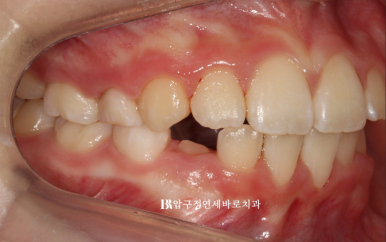

22.11.23

병원에 처음 온 날 모습입니다.

문제점을 나열해보자면

과개교합 (앞니가 깊게 물림)

덧니 (삐뚤빼뚤)

후속 영구치가 나올 공간 부족

그리고 아이의 개인적인 문제점은 당장 한달뒤에 외국에 나가 6개월 후 귀국

이런상황들에 맞춰 치료계획을 만들었습니다.